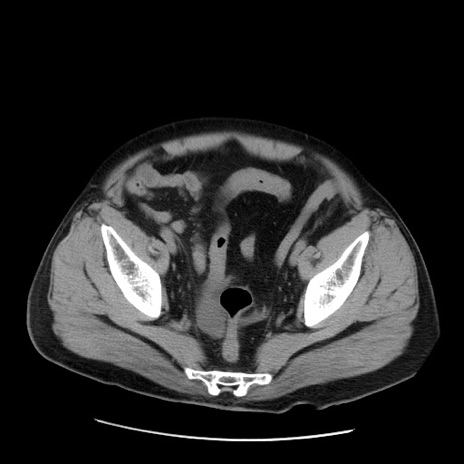

症例20(横断像)

【症例】 60歳代男性

【主訴】 腹部膨満、嘔吐

【現病歴】5日前頃より倦怠感を認め食事量減少し4日前の朝嘔吐、食事摂取困難となった。 3日前近医受診し点滴施行され整腸剤などを処方された。 当日他院を受診し、腹部膨満著明、炎症反応の上昇(CRP10.8、WBC11200)あり、紹介受診となる。

【身体所見】 意識JCS1 受け答えがはっきりしないBP 111/57mHg、 P 67bpm、、BT35.2°C、SpO2 97%(RA)、 腹部:膨隆、打診で鼓音あり、全体的に圧痛有り、腸蠕動音(-)、反跳痛ははっきりせず。

【データ】WBC 11400、CRP 14.20